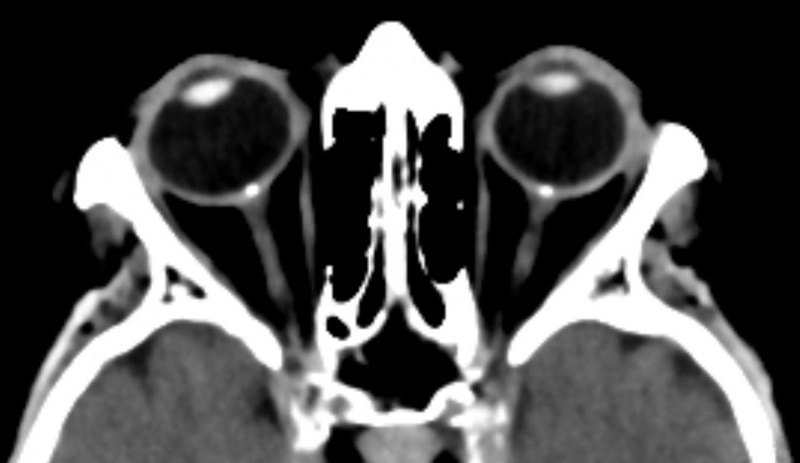

Description Bilateral optic disc drusen (optic nerve head drusen) in computed tomography of the orbit seen as dense spots at the optical disc. 73y female.

Date 2 February 2016 Author Hellerhoff